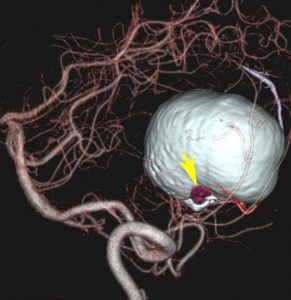

フォンヒッペルリンドウ病に合併した大きな右小脳半球血管芽腫です。大きなものでは静脈環流障害(鬱滞)のために脳浮腫を来すことが多いし,その分,手術時の静脈圧が高くて止血が難しいと考えなければなりません。水頭症を呈して症状は重篤でしたが,右後頭窩開頭で比較的簡単に全摘出できて回復しました。小脳半球に生じるものは手術で大きな障害を残すことはほとんどなく術後の症状症状の回復も順調なことが多いです。

同じ患者さんです。上記の手術の5年後に新たな血管芽腫が激しく増大しました。これは小脳虫部なので両側の上小脳動脈がfeeding arteryとなります。bilateral occipital transtentorial approachという特殊な手術方法でしか摘出できません。幸いこの腫瘍も無事に全摘出できました。